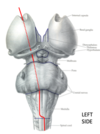

Name the tract.

If lesionned at thoracic levels of the spinal cord, the tract shown in red could lead to:

A. Weakness of the left leg

B. Weakness of the right leg

C. Numbness of the left leg

D. Abnormal pain sensation on the surface of the left leg

E. ataxia

Lateral Corticospinal Tract

If lesionned at thoracic levels of the spinal cord, the tract shown in red could lead to:

A. Weakness of the left leg

In the images, locate the lateral Corticospinal tract.

Name the levels and locate the lateral corticospinal tract within them.